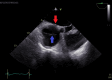

The diagnosis of atrial septal defect (ASD) may be delayed until adulthood or even later in life as it is a well-tolerated congenital heart disease. If patients are not examined and investigated well in childhood, the diagnosis may be delayed until later in adulthood when patients present with palpitations and sometimes dyspnea due to the right chambers dilatation from right ventricular volume overload. In this report, we present a case of a 50-year-old female patient with symptoms of heart failure and atrial fibrillation who was found to have dilated right cardiac chambers, dilated pulmonary artery, severe tricuspid regurgitation, pulmonary hypertension, and a pulmonary-to-systemic flow ratio (Qp/Qs) of more than 1.5 by transthoracic echocardiography and Doppler, indicating left to right shunt at the atrial level. However, transthoracic echocardiography could not visualize the defect, and two-dimensional (2D) transesophageal echocardiography was done in this patient and documented the presence of a sinus venosus ASD with an incomplete cor triatriatum dexter membrane; all four pulmonary veins were identified going to the left atrium. Since the presence of an incomplete cor triatriatum dexter membrane (despite causing no symptoms) makes the percutaneous closure of the sinus venosus ASD and the percutaneous repair of tricuspid regurgitation very difficult, we decided to advise surgical ASD closure and tricuspid valve repair for the patient.